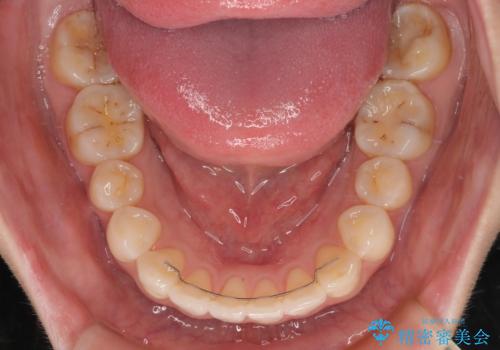

舌のトレーニングは不十分でしたが、1年半ほどで治療を終えることができました。

舌の突出癖が残っていると、容易に後戻りしてしまうため、トレーニングは継続するように指導しています。